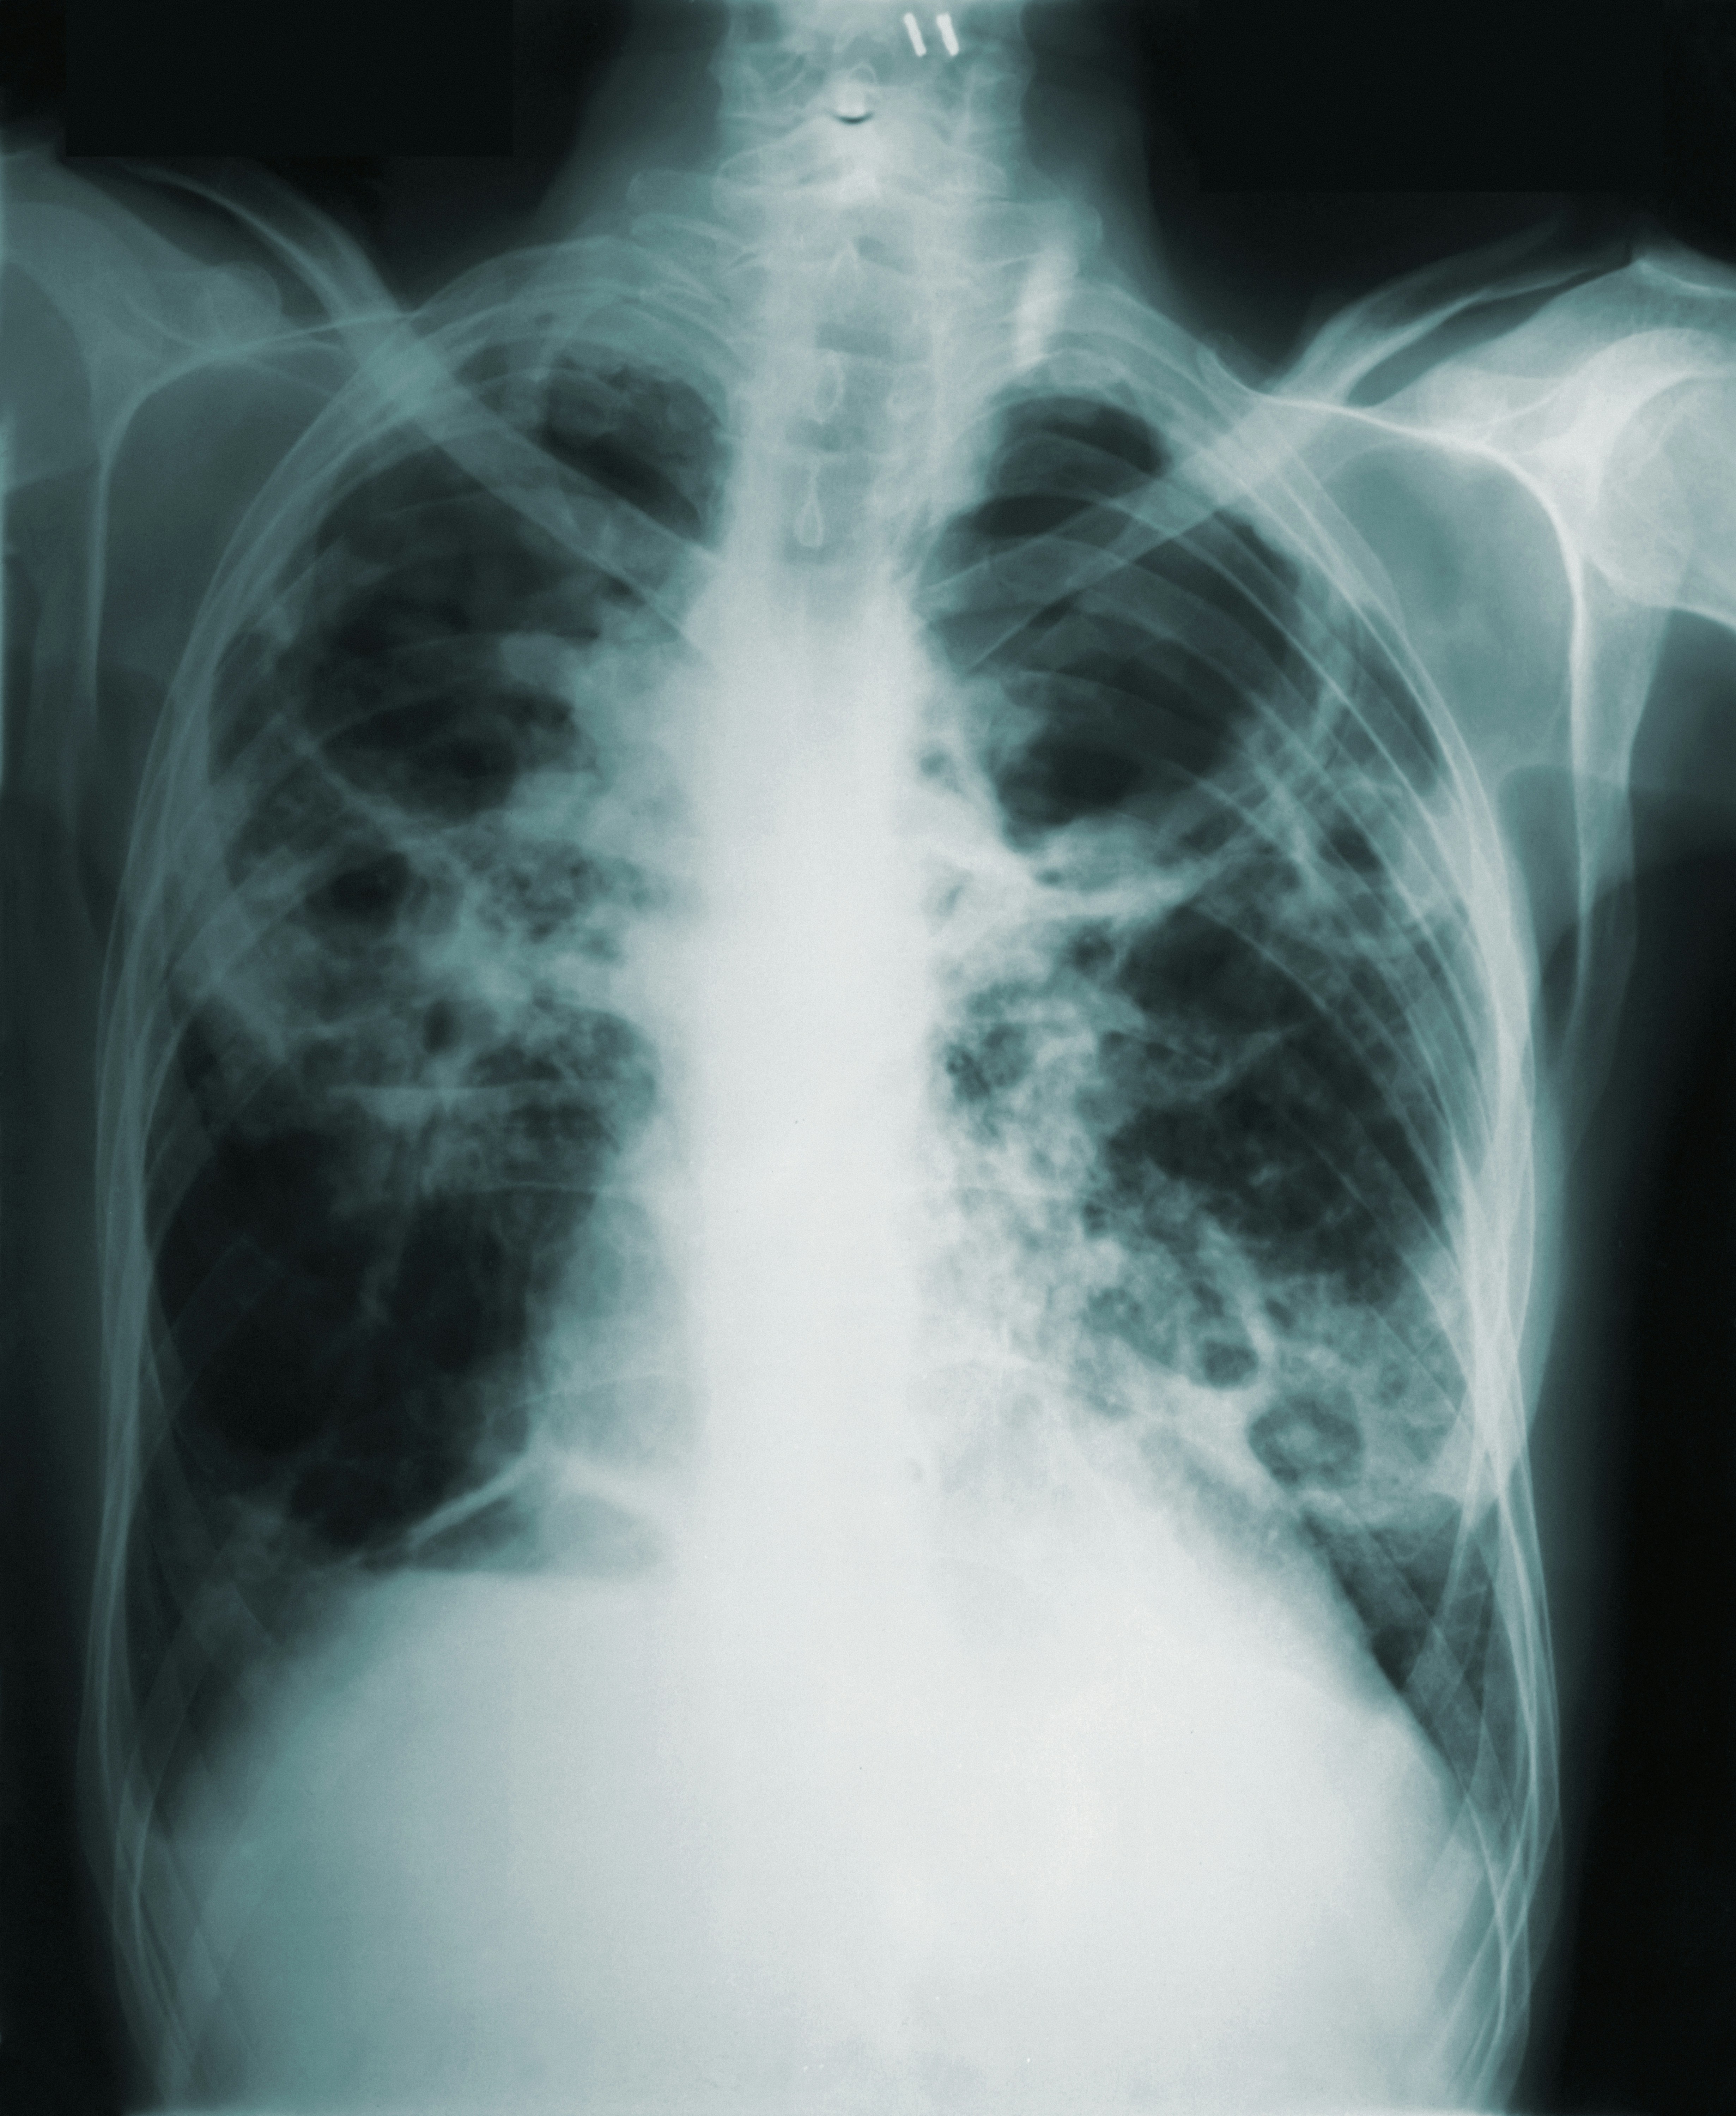

- 발열(37.5℃ 이상) + 기침이 동반될 경우 → 내과 방문 후 폐렴 여부 확인